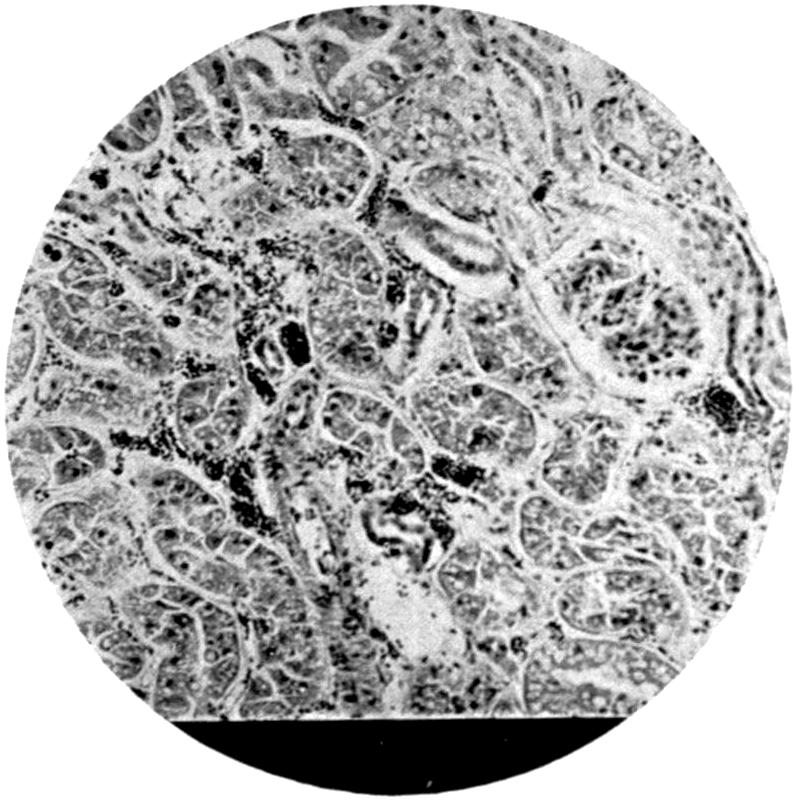

Plate III. 95